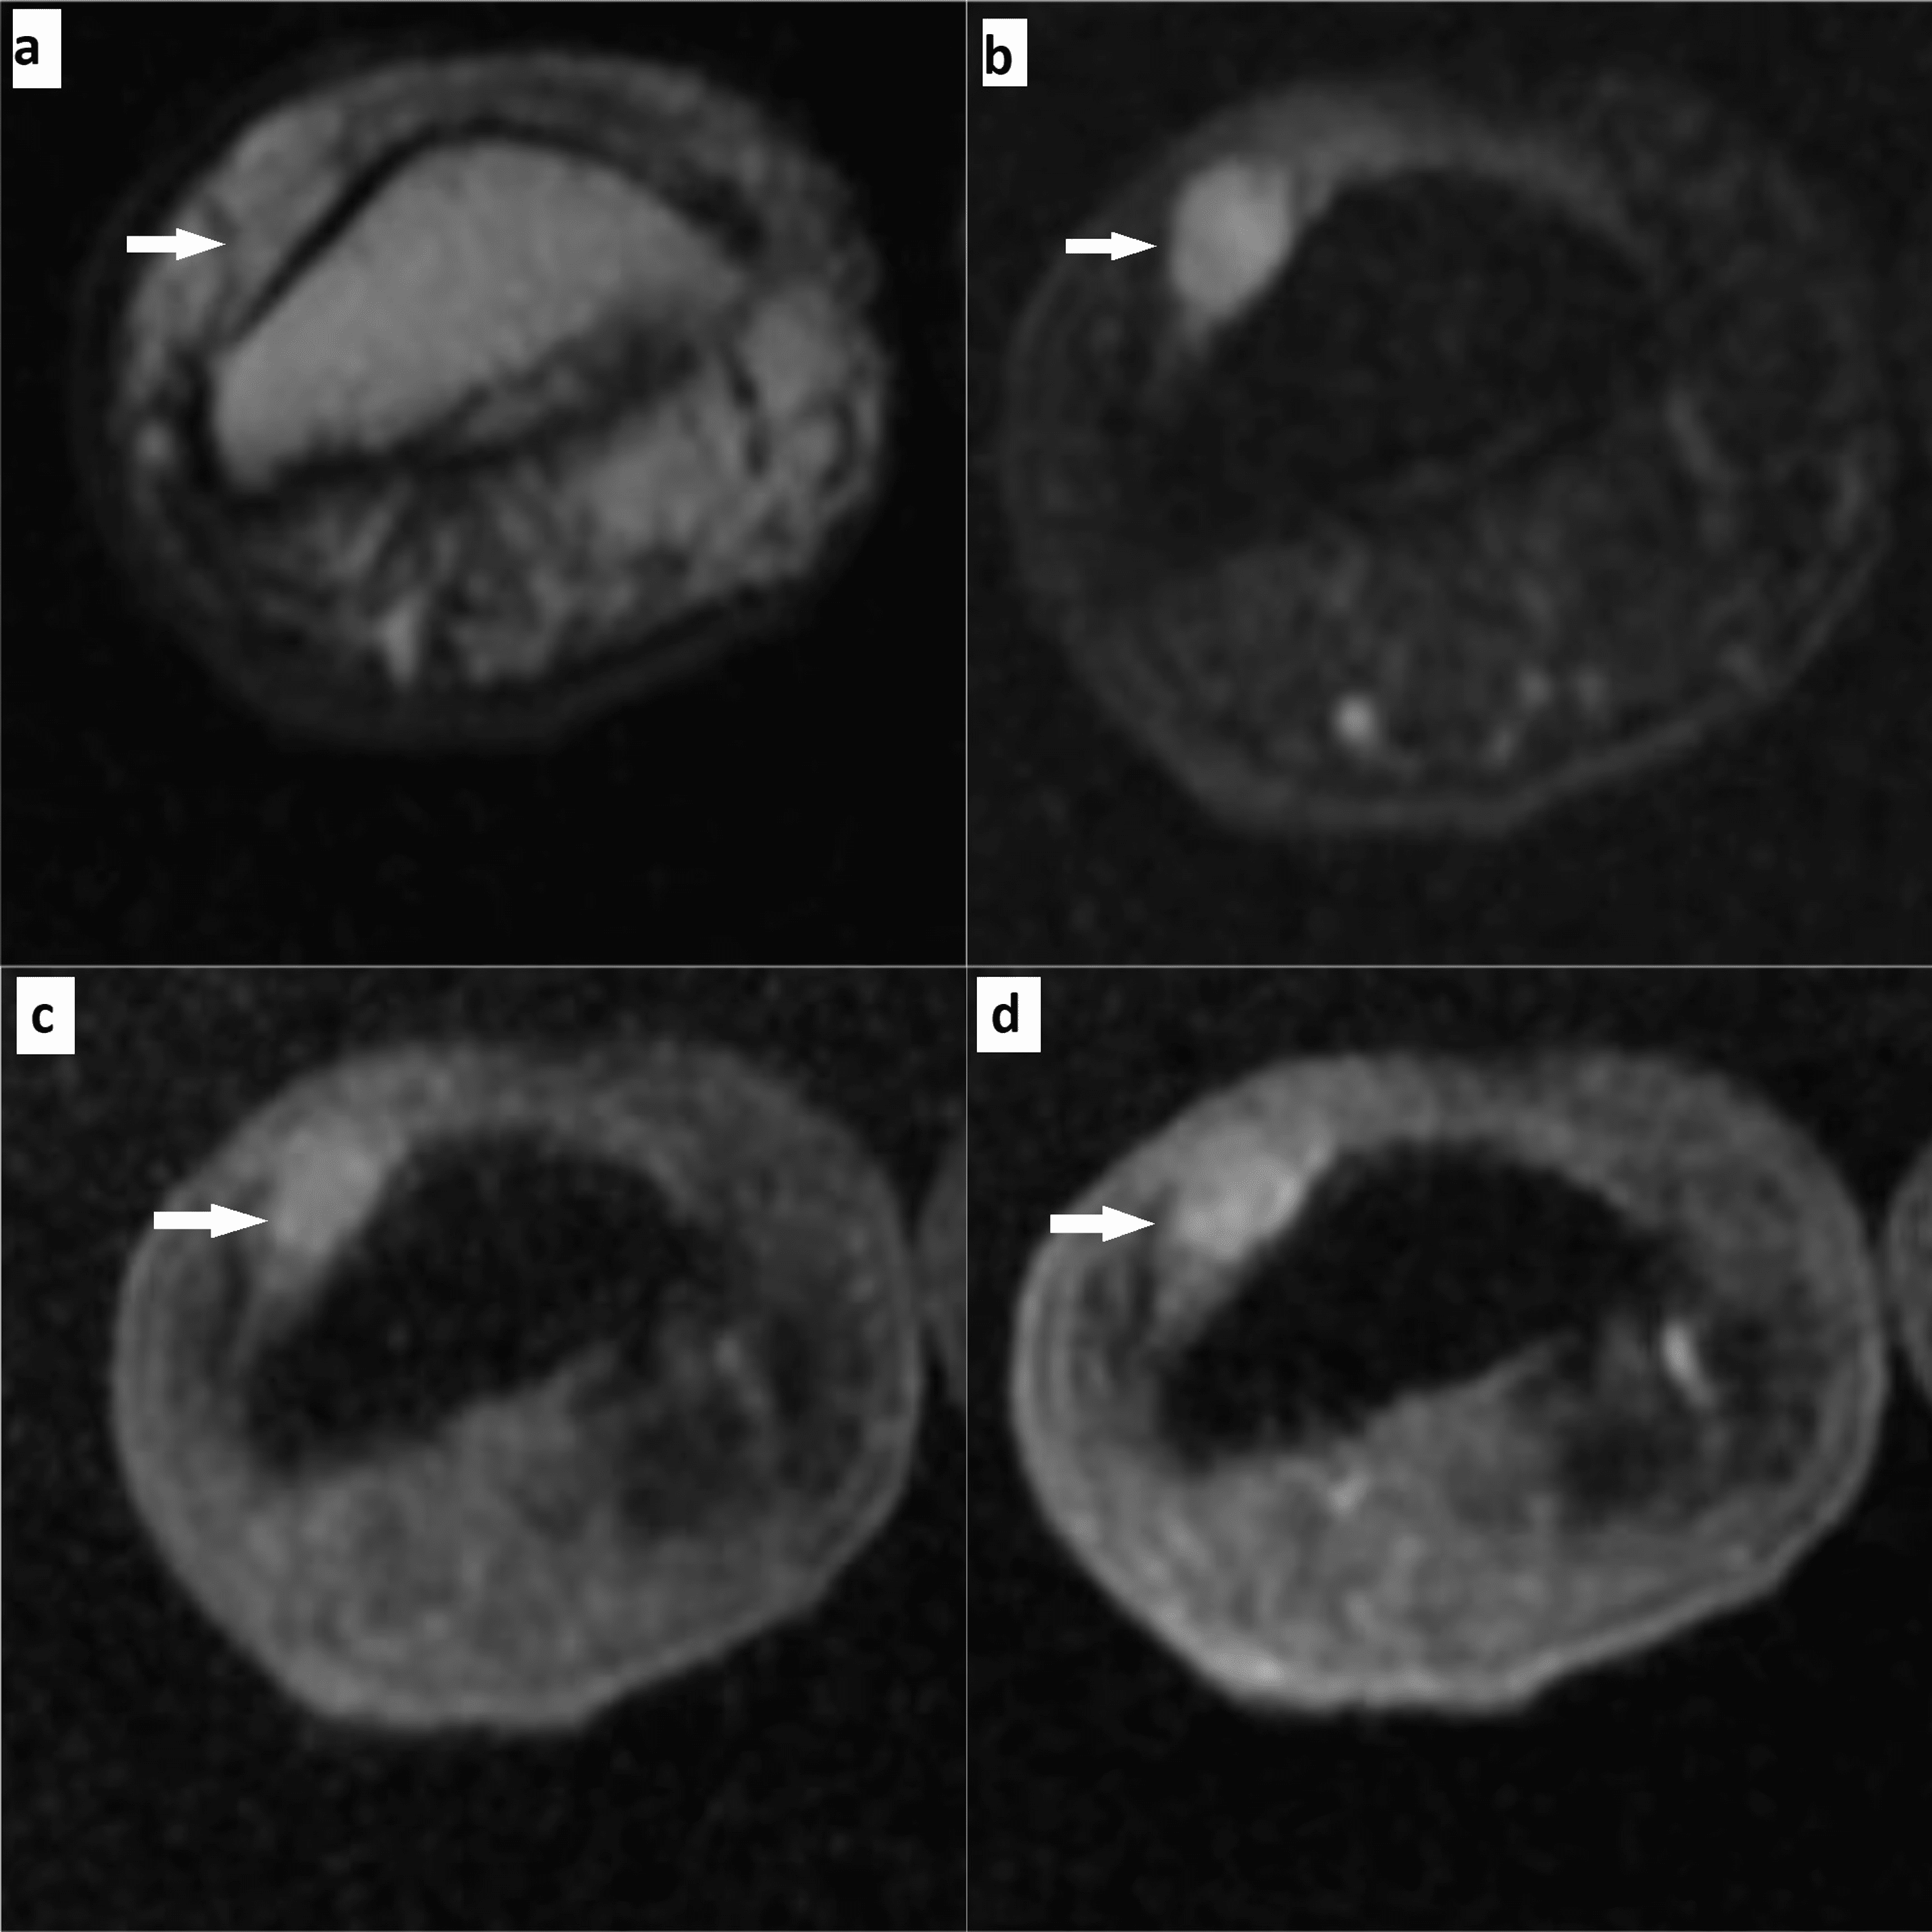

From www.cureus.com

Cureus Hand and Foot Glomus Tumors Significance of MRI Diagnosis Types Of Foot Tumors Soft tissue sarcoma of the foot is an extremely rare tumor. Kirby zones are used to categorize the location of both soft tissue and osseous tumors. Kirby anatomic zones of the foot and ankle. While many tumors of the feet aren't cancer, it’s important to contact a doctor to confirm. The following chapter looks in detail at the more common. Types Of Foot Tumors.